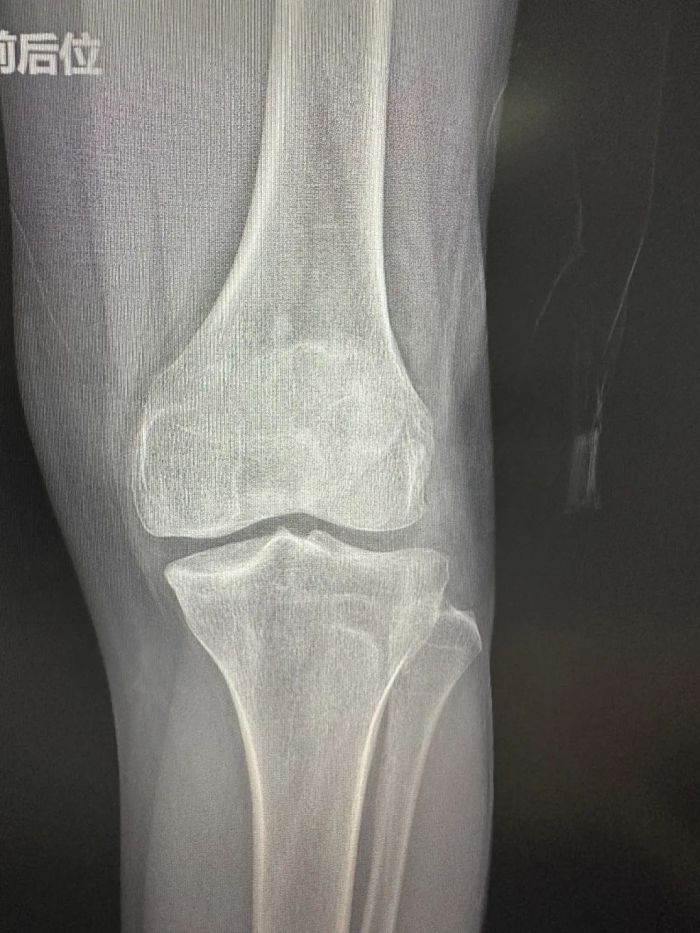

患者蒋先生由于职业原因,长期忍受膝关节疼痛的痛苦,严重影响了日常生活质量。经过中南大学湘雅二医院保膝团队专家吴韧教授及中南大学湘雅二医院桂林医院骨科一病区(关节、脊柱)团队的详细诊断和评估,认为单髁置换手术是目前最适合该患者的治疗方案。

患者术前膝关节情况